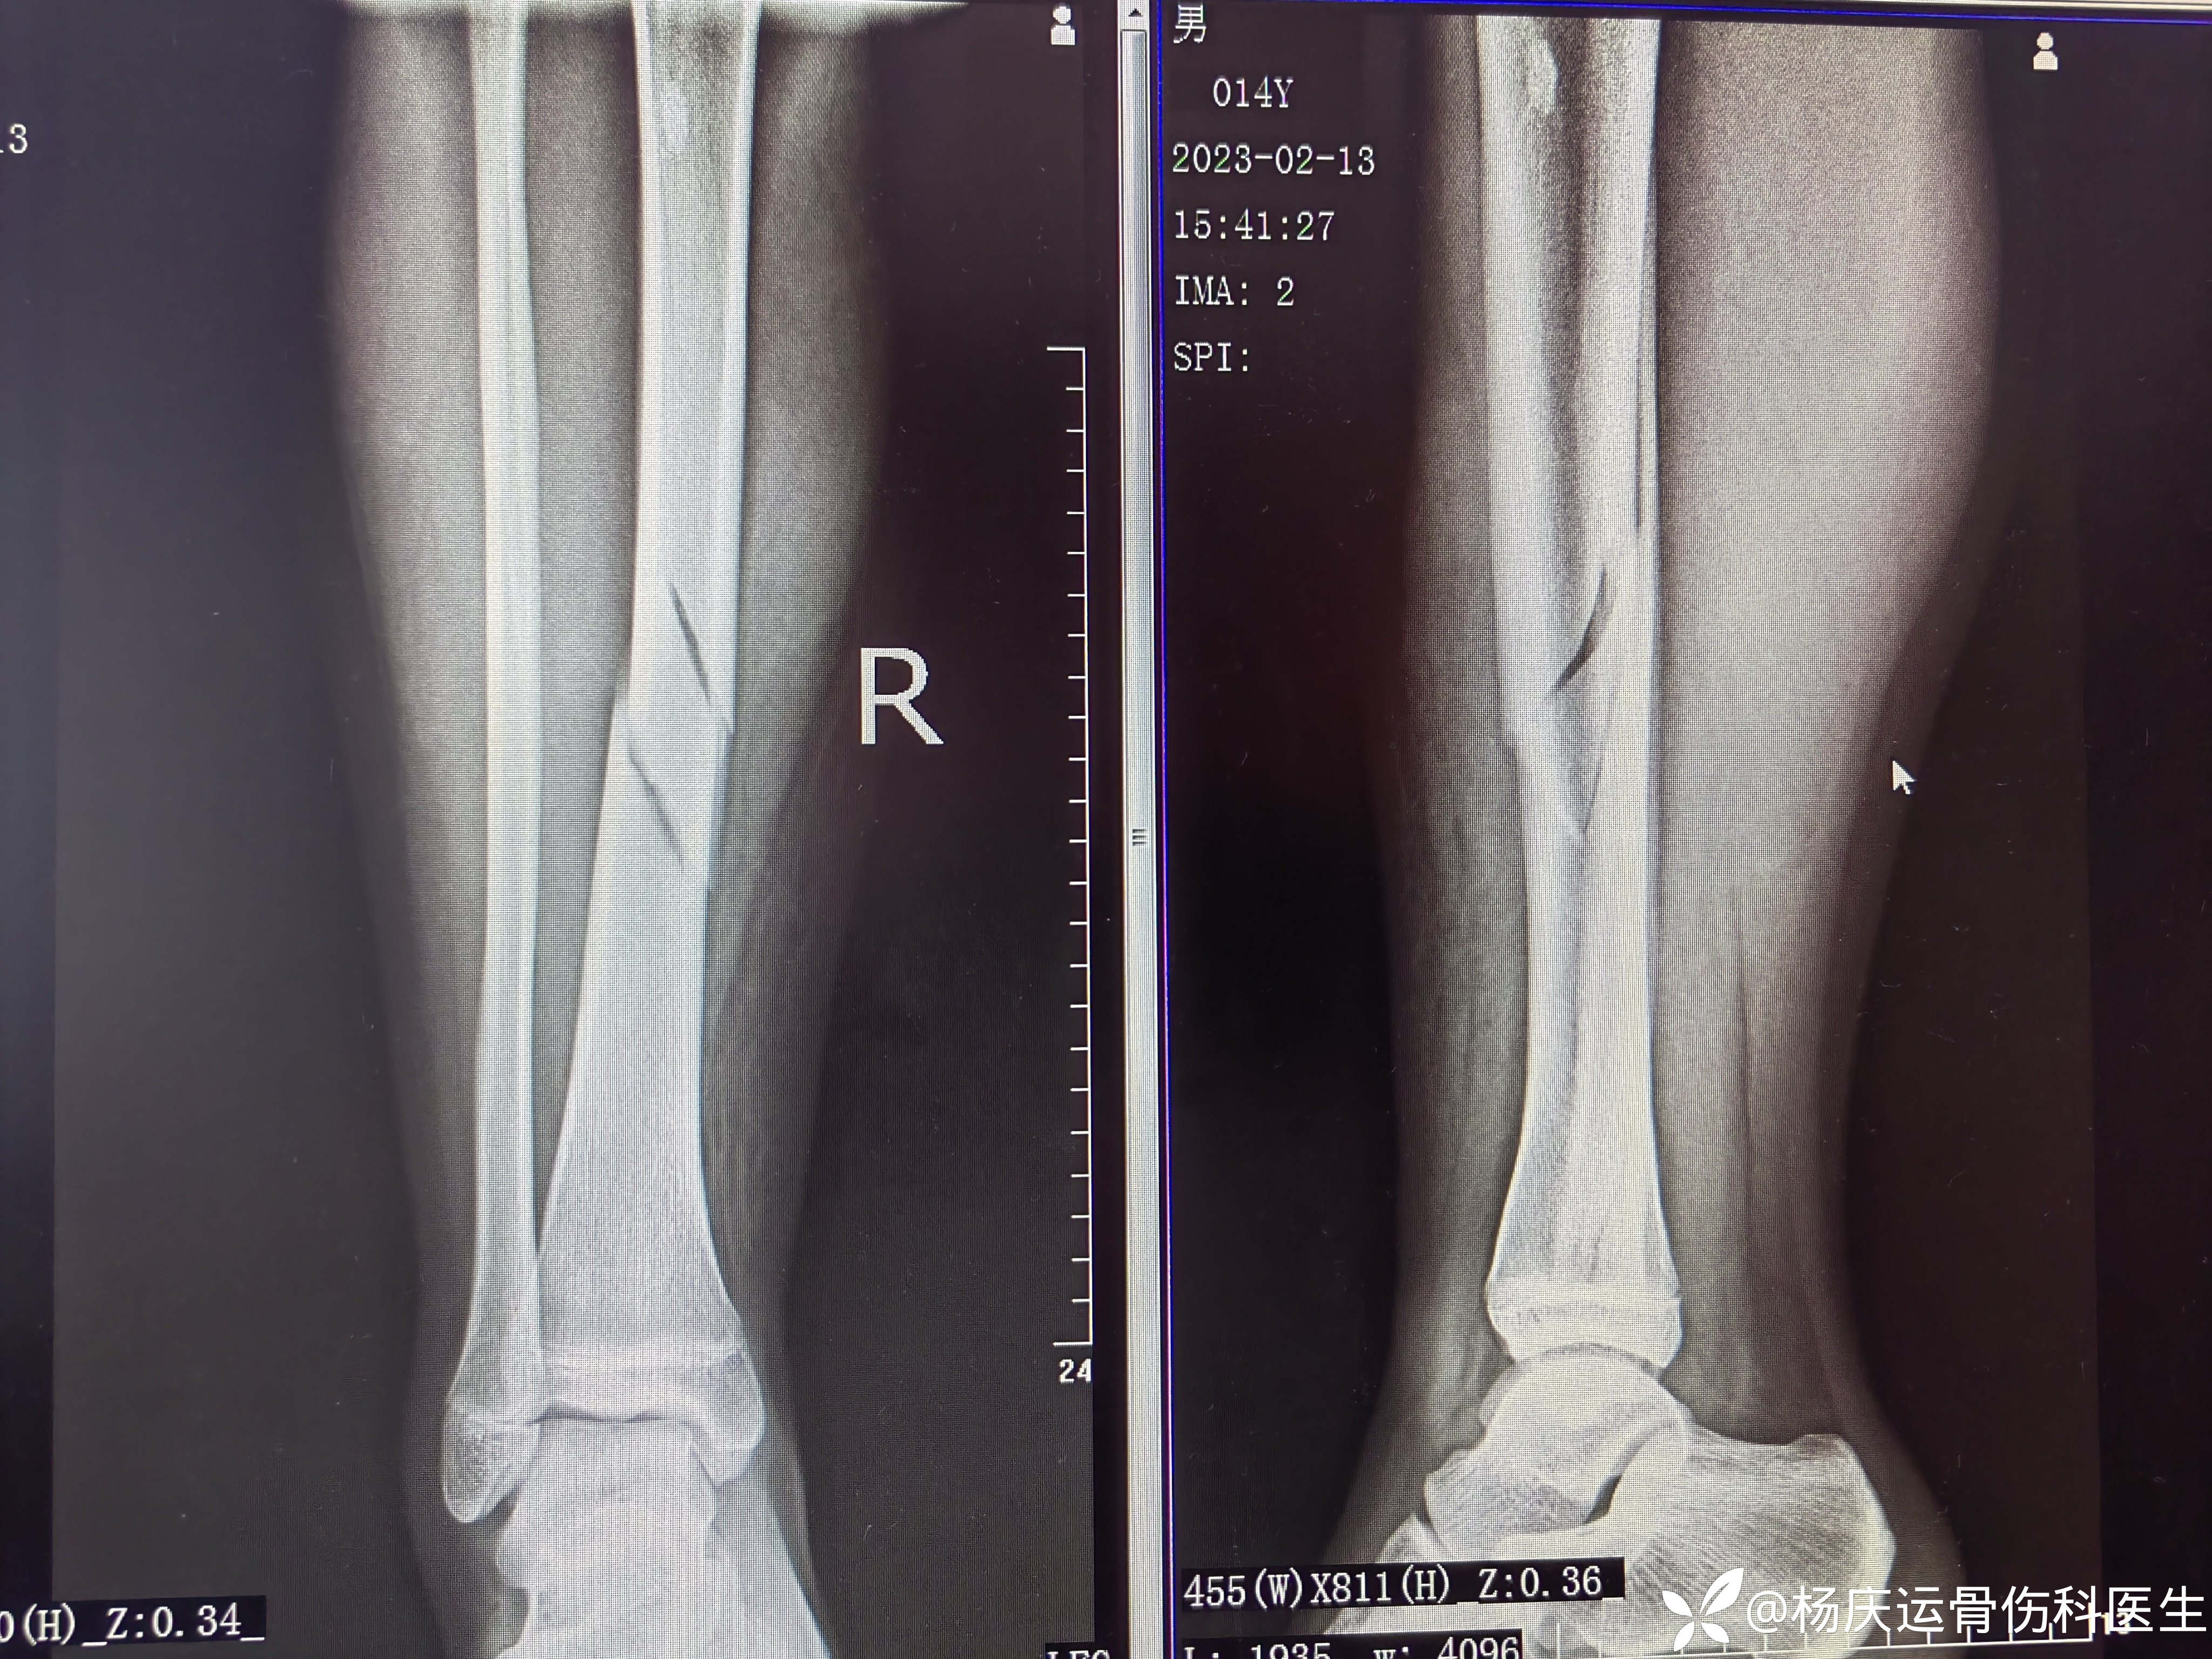

初步诊断:右胫骨中下1/3段骨折

治疗方案:闭合复位夹板外固定治疗

首诊片